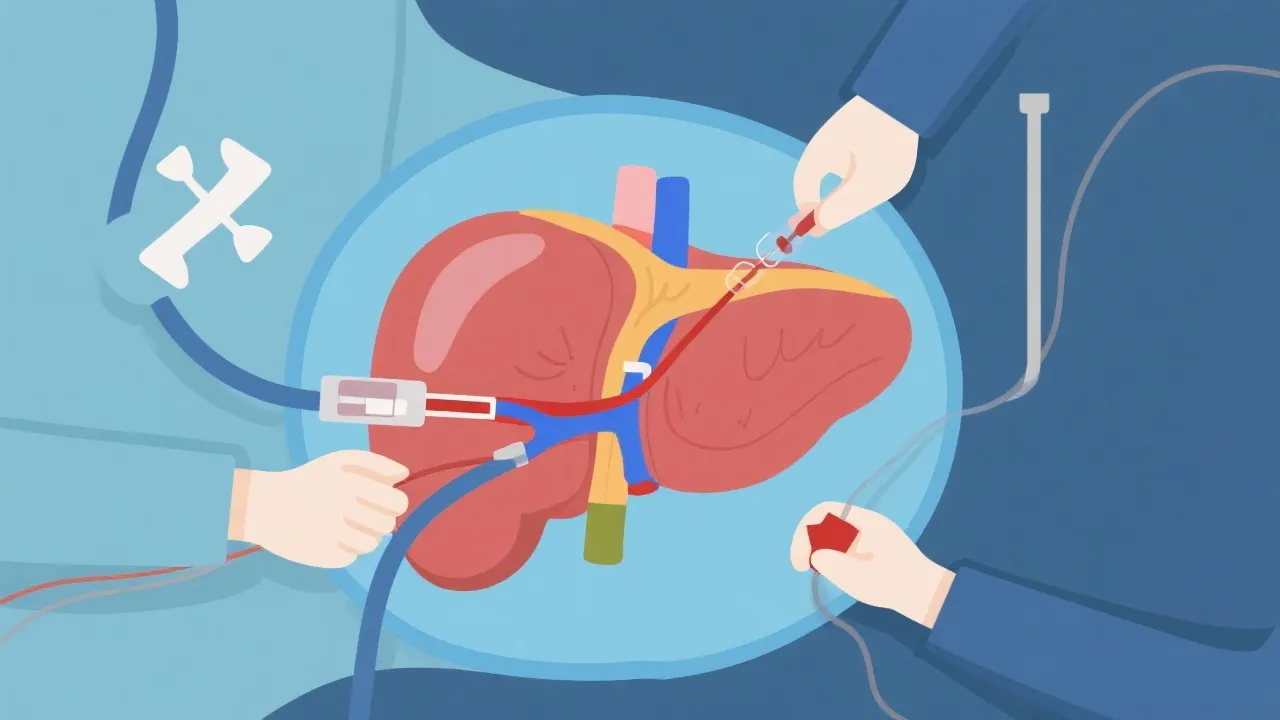

Understanding Hepatitis E and Liver Transplant

Understanding Hepatitis E and Liver Transplants

Understanding Hepatitis E and Liver Transplants

Understanding Hepatitis E and Liver Transplants

Understanding Hepatitis E and Liver Transplants

Hepatitis E and Liver Transplant

Understanding Hepatitis E and Liver Transplant

Understanding Hepatitis E and Liver Transplants

Navigating Hepatitis E and Liver Transplant

Navigating Hepatitis E Liver Transplants

Hepatitis E and Liver Transplant Insights

Hepatitis E and Liver Transplant